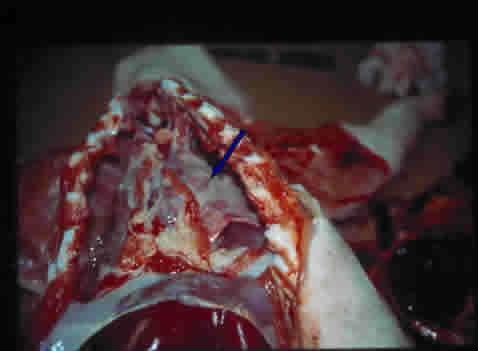

. Cavité thoracique : péricardite fibrineuse, pleurésie fibrineuse (pas d'œdème pulmonaire).

Epanchement

pleural

|

Péricardite

+ pleurésie

|

Poumons

avec dépôts de fibrine

|

|

Poumons

avec dépôts de fibrine

|